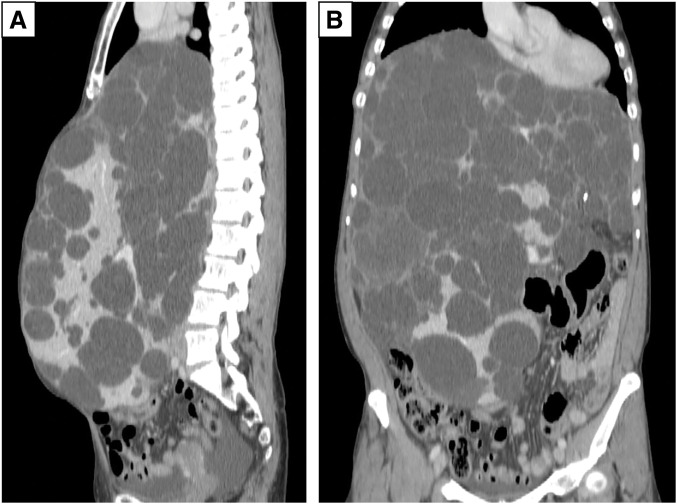

Case presentation: A female patient in her 40s with a history of autosomal dominant polycystic kidney disease presented with progressive liver cyst enlargement (Gigot type III, Qian classification Grade 4), which led to decreased activities of daily living and intracystic hemorrhage. The patient underwent a deceased-donor liver transplantation. During mobilization of the liver from the right side of the diaphragm, the patient experienced sudden onset of pneumothorax. Incision of the diaphragm revealed a cystic structure containing a hematoma, suggesting pneumatocele formation. The pneumatocele was not resected during the ongoing operation; instead, thoracic drainage was performed as the primary intervention. Postoperatively, no air leakage was observed, and the thoracic drain was successfully removed on POD 12. The pneumatocele, which measured approximately 10 × 10 × 7 cm, showed no signs of infection, and was monitored without additional surgical intervention. On POD 19, a fever prompted further evaluation, and CT-guided cyst aspiration for culture was performed, which revealed no evidence of infection. Acute T-cell-mediated rejection was observed on POD 27, and a steroid pulse was administered, but even after that, the pneumatocele gradually decreased in size without any signs of infection.